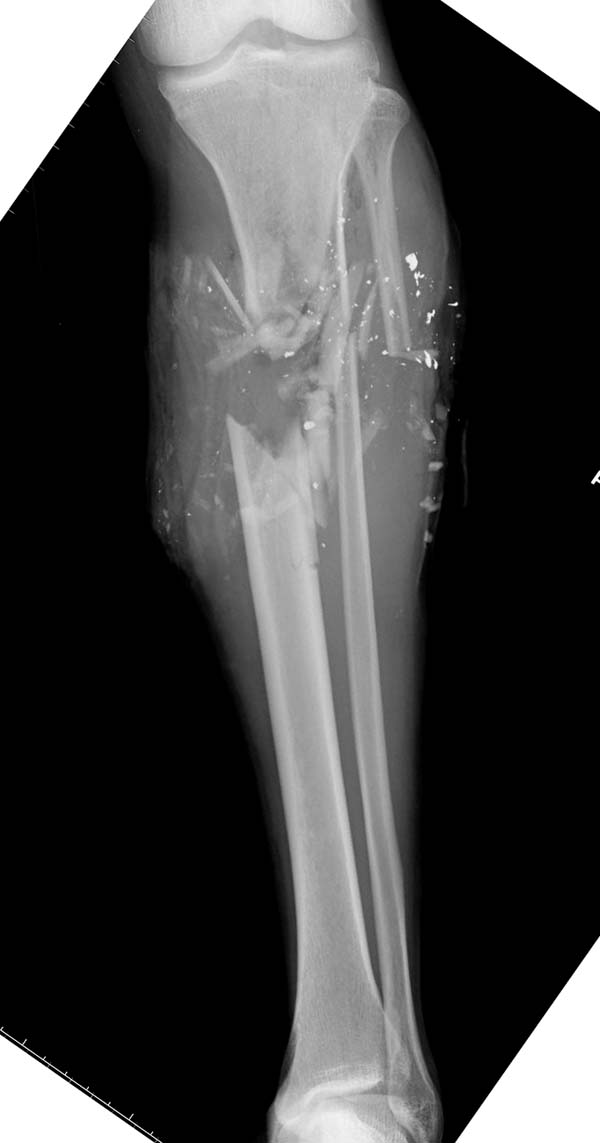

>чего вы ждете? закрывайте пока что есть с грануляциями

Под воздействием вакуума образовалась готовая к кожной пластике грануляционная поверхность, но не стал бы спешить, потому что посаженная на кость кожа имеет плохое питание и легко травмируется. В данном варианте, кроме закрытия дефекта необходимо решить проблему сращения кости, потому что в зоне с пониженным кровообращением восстановление происходит медленнее и в большинстве открытые, инфецированные переломы осложняются атрофическим ложным суставом!

Нехватка кровообращения решается подведением “спасательной подушки” из мышцы. Усиленное кровообращение легко справляется инфекцией, а также облегчает кожную пластику. Ротируется мышца, а на нее можно сажать кожу, и проводить вакуумирование до периода приживления кожи...

Здесь примерный протокол лечения открытых ран с дефектом кости и мягких тканей. Применение вакуума с первых дней предупреждает

инфецирование раны и, не ожидая закрытия дефекта, можно проводит фиксацию даже внутрикостными фиксаторами. Затем можно продолжить процедуры по закрытию мягкотканннего дефекта.

Такая этапная тактика: Irrigation and Debridement, наружный фиксатор, вакуум, гвоздь, покрытие дефекта с ротацией medial gastroc и c кожной пластикой позволяет более агрессивно, в короткие сроки, создать более благоприятные условия для восставления переломов с дефектом мягких тканей